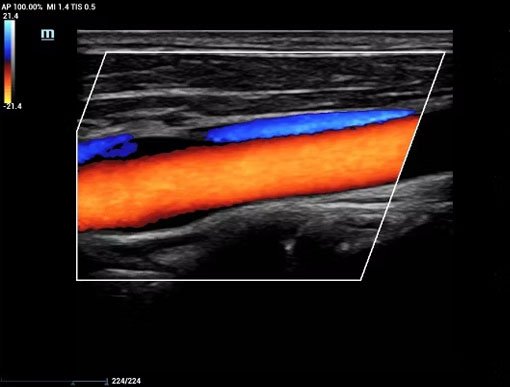

A Color Doppler Ultrasound System is an advanced diagnostic imaging technology used to visualize blood flow within arteries and veins in real time. By combining conventional ultrasound imaging with color-coded Doppler flow analysis, it enables accurate assessment of vascular health, cardiac function, and organ perfusion, making it an essential tool in modern medical diagnostics.

Color Doppler systems use the Doppler effect to measure the speed and direction of blood flow. Blood flow is displayed in different colors over the grayscale ultrasound image, allowing clinicians to easily identify normal and abnormal circulation. Advanced modes such as Power Doppler, Spectral Doppler, and Tissue Doppler provide detailed hemodynamic information.